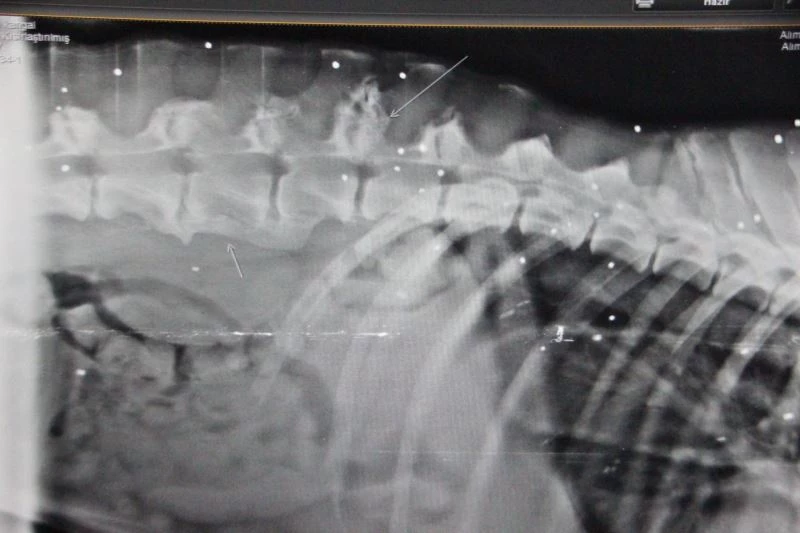

Bodrum’da halsizliği nedeniyle bakımevine gönderilen köpeğin vücudunun röntgenini görenler şok oldu. Onlarca saçma bulundu köpeğin vücudundan çıktı.

Edinilen bilgiye göre Bağla bölgesindeki bir sitede kangal cinsi 5-6 yaşlarındaki bir köpek, bitkin halde bulundu. İştahsızlık ve kusma şikayetleri bulunan ve dışarıdan bakıldığında bir yarası görünmeyen köpek, Turgutreis Bakımevi’ne gönderildi. Köpek, daha sonra ileri tetkik ve tedavi için Yalıkavak Terapi Veteriner Kliniğ’ine götürüldü. Yapılan kontrollerinde eklem hastalığı ve kan paraziti teşhis edilen köpeğe ayrıca röntgen çekildi. Çekilen röntgen sonucunda köpeğin vücudunda onlarca saçma ile yaşadığı ortaya çıktı. Ne zaman vurulduğu bilinmeyen köpeğin tedavisi sürüyor.

Köpeği vuran kişi veya kişilerin bulunması için ise çalışma başlatıldı.